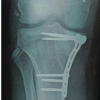

A 55 year-old male patient presented to outdoor clinic with gradually increasing swelling on anteromedial aspect of the right knee joint with intermittent episodes of pain on prolonged standing and walking since 8 months. Proper history, clinical examination, digital radiographs, and routine investigations were performed. Digital radiographs (anteroposterior and lateral views) showed swelling arising from anteromedial aspect and lucency around cortex of tibia (Fig. 1). Thereafter, MRI of knee joint was performed which showed well-defined cystic lesion with internal septations arising from medial aspect of tibia with soft-tissue extension and measured around 4 × 3 cm (Fig. 2).